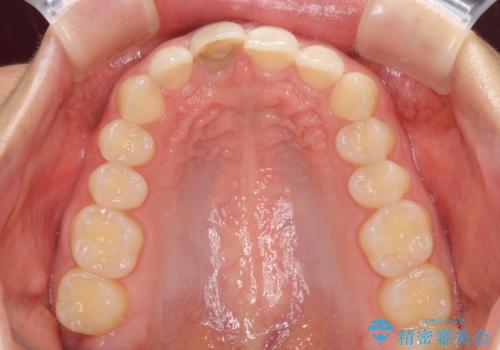

- 中学生の時にぶつけて神経を取り除いた前歯の変色が気になるとのことで来院された患者様です。

レントゲン写真より、歯根の炎症が認められなかったため、ファイバーコアによる土台築製後、オーダーメイドタイプのオールセラミッククラウンにて補綴することとしました。

あっという間に気になっていた変色が解決し、早く治療を始めれば良かったとおっしゃっていました。

オーダーメイドタイプのクラウンを選択いただいたので、まるで天然の歯と見間違うほど自然に仕上がり、患者様には大変満足していただきました。